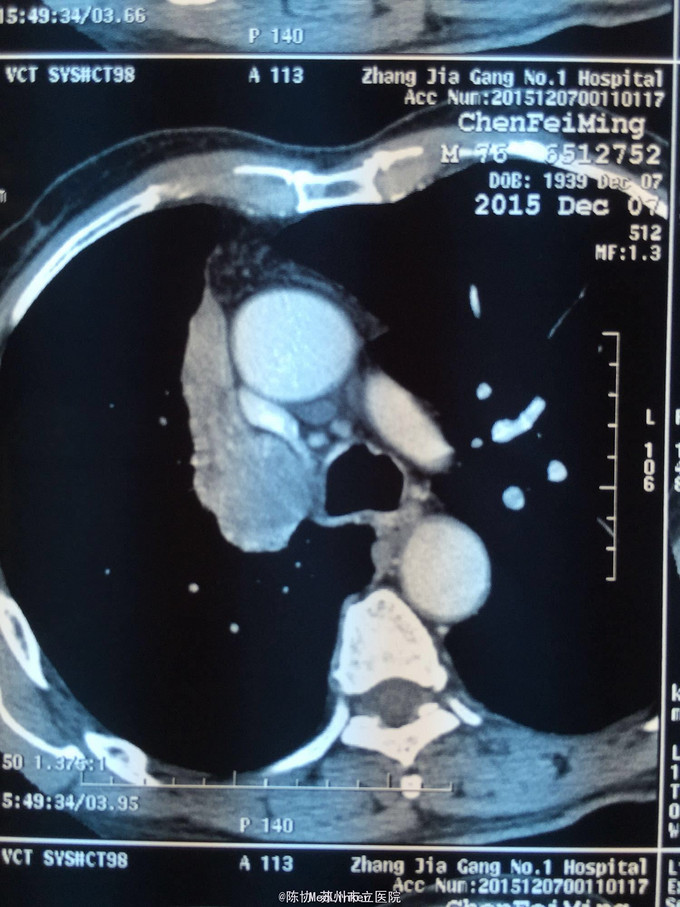

主诉:体检发现右上肺不张半月 77岁男,半月前体检发现右上肺不张,无不适。无消瘦,无咳血,无干咳。去年4月右上肺炎,抗生素治愈,当时CT未见肺肿块。入院支气管镜发现右上支气管开口组织增厚闭塞,开口近侧有隆起约3x3平方毫米,取活检5块病理示中度非典型增生。CT提示在右侧主支气管外侧有30x30平方毫米块影,压迫右上支气管开口处。三大常规和生化检查正常,肿瘤指标正常,TAP正常。

右侧中央型肺癌 重做支气管镜,精于定位找到病症组织,获得病理诊断来指导治疗。 胸外科医生不建议手术,理由是肿瘤位置靠近主支气管和气管,袖状切除不一定看干净。 请问正确的诊断,和比较合理的治疗方法是什么?求助大家思考评论